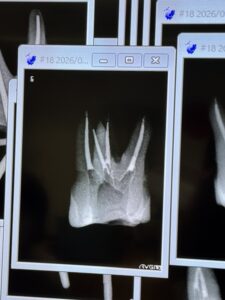

地方都市から来られているI先生のテストケースは以下だ。

日本では非難の?対象になるがアメリカだと絶賛されるシーラーパフの確認できる根管充填がなされている。

この事実一つとっても日本はもはや周回遅れと言ってもいいだろう。

そして一言、上手い!

下顎の近心根は術前にCBCTを撮影し、MB,MLが合流していると認識して合流の位置を確認して根管充填している。

これが

“わかっている人”

のなせる技だ。

全く問題がない。